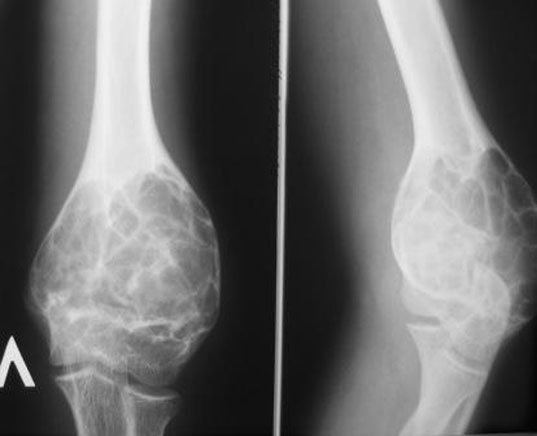

Рентгеновские снимки саркомы плечевого сустава